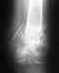

Re: Избежать артродеза голеностопного сустава

В лечении надо использовать не идеи, а доказавшие свою пользу методики. Действительно, в этой ситуации наиболее быстрый и надежный путь достичь опорной и безболезненной конечности - это артродез. Бессмысленное выражение "ампутация сустава" - это дилетантские эмоции. Речь не о тазобедренном или коленном суставах. Биомеханика походки после замыкания голеностопного или подтаранного суставов практически такая же, что и после восстановительных операций.

Вместе с тем, от посттравматического артроза не умирают, и если выраженность болезненных проявлений не превышает порог приемлемости для пациента, операция не нужна (пока).